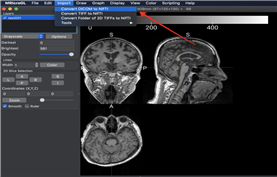

② 뇌영상 데이터 (.nii / .nii.gz / .csv)

뇌영상 데이터

구분 항목 대상자 비고

뇌구조 MRI 영상 TI 254명 1인당 362개 정보

뇌기능 MRI 영상 EPI 254명 1인당 7000장 이상